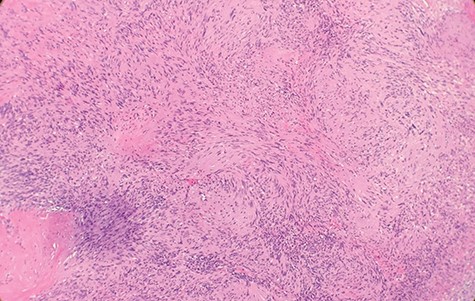

Macroscopically, the tumor appeared encapsulated, rubbery and pink-tan in color. Microscopic examination reveals that tumor composed of biphasic spindle hypercellular Antoni A areas and hypocellular Antoni B areas (Fig. 1). Higher magnification reveals that spindle tumor cells are narrow, elongate, wavy with tapered ends interspersed with collagen fibers (Fig. 2). Immunohistochemical staining revealed that most tumor cells reacted strongly for S-100 protein (Fig. 3). Combined with immunohistochemical profile, these histological features are diagnostic of benign schwannoma. Patient was discharged home on the same day as the operation. At the 1-month follow-up, he was symptom free, without any pain or sensory disturbances.

Microscopic examination reveals that tumor composed of biphasic spindle hypercellular Antoni A areas and hypocellular Antoni B areas (×2).